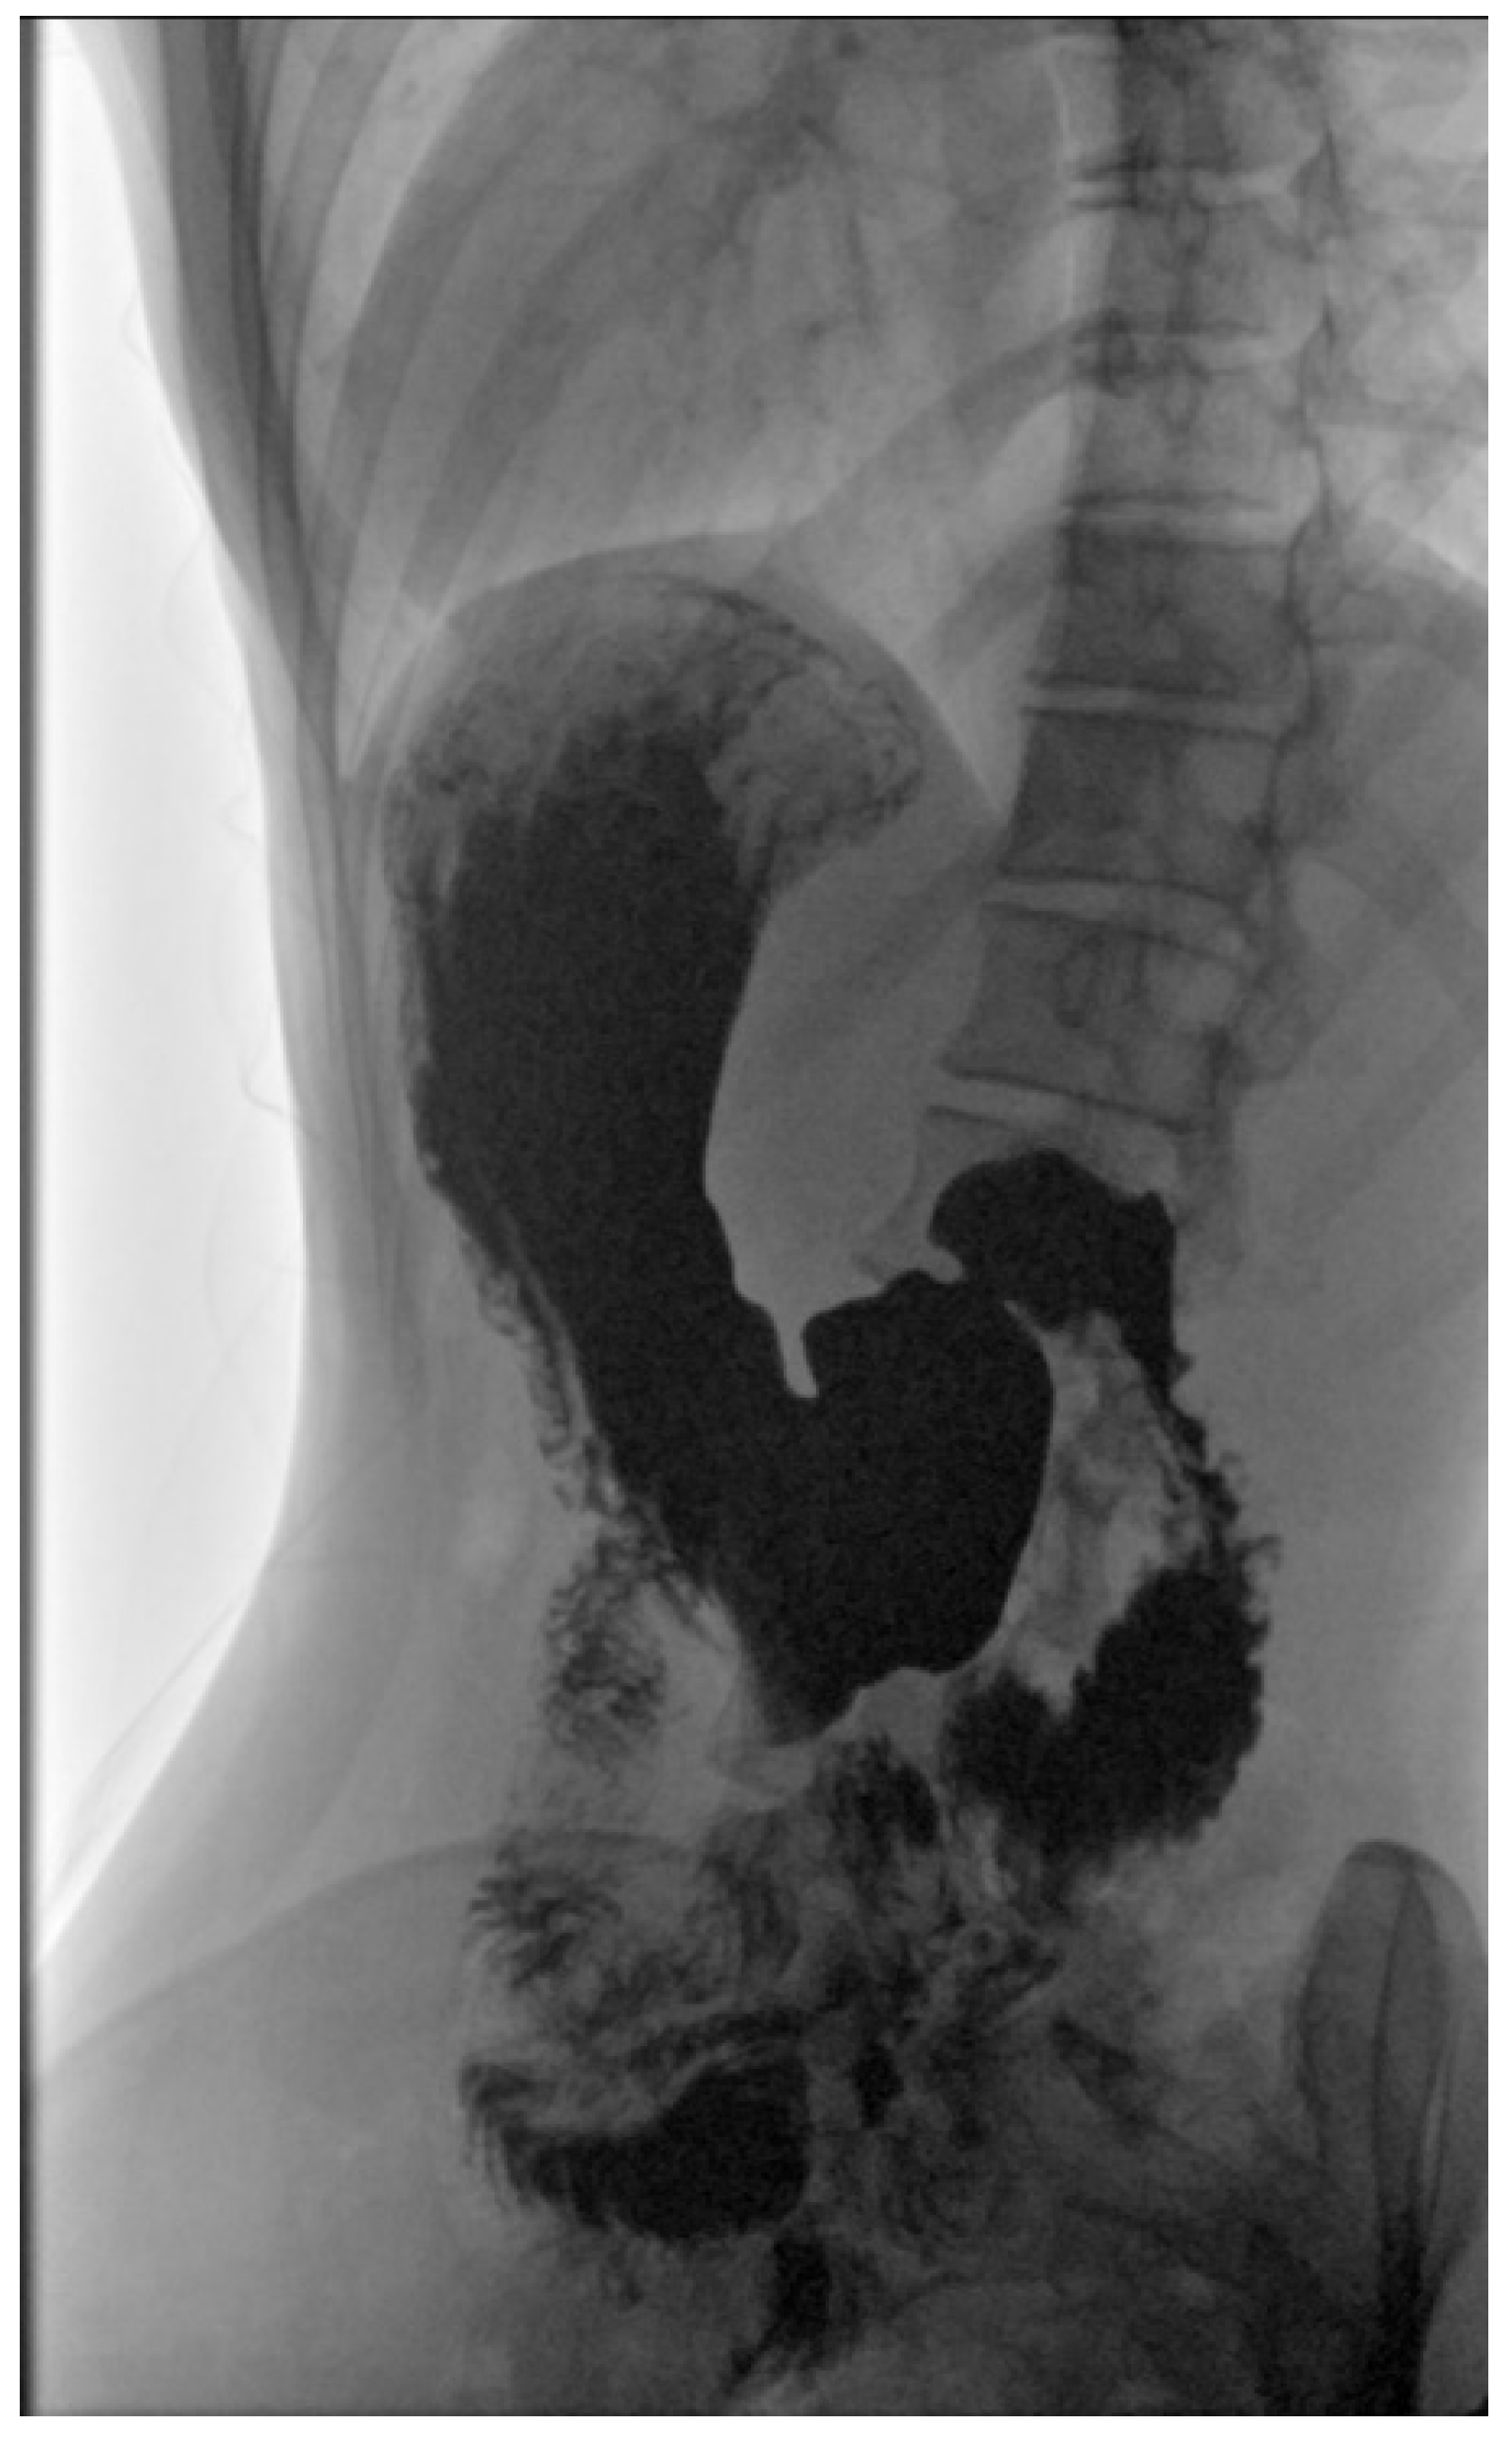

2.4. Physical Examination, Laboratory Tests’ Results and Imaging Studies

2.5. Diagnosis and Treatment